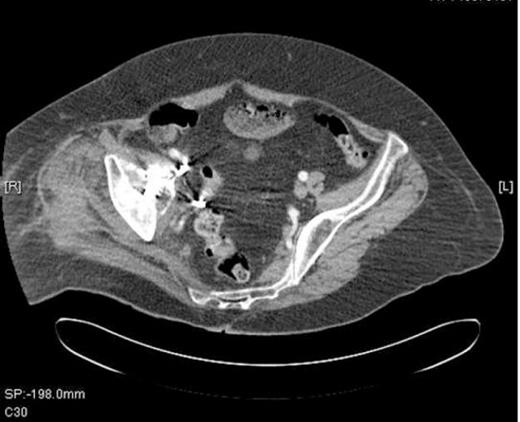

The acetabular screws were seen projecting medially into the pelvis with the anterior screw closely abutting the external iliac artery and vein causing compression (Figure 2).

A CT Scan of the pelvis showing compression of external iliac vein by acetabular screw